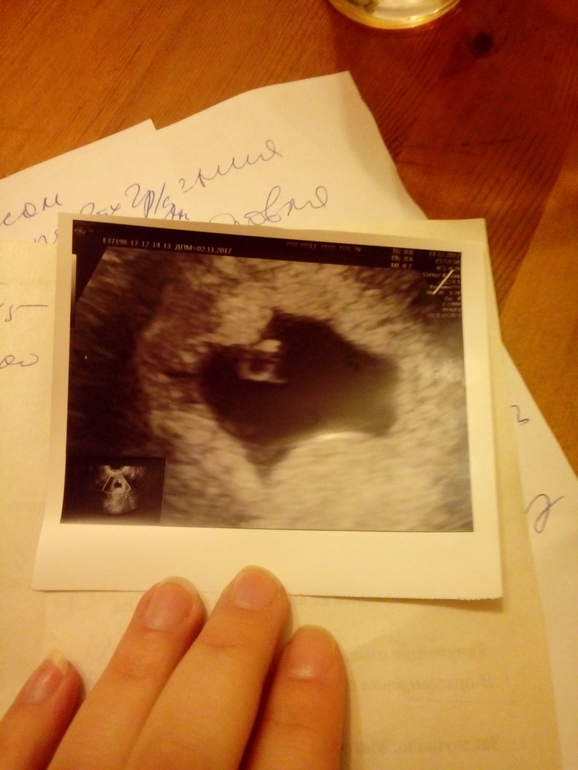

КТР не соответствует сроку.

Вопросы про УЗИ, обследования и анализы: что, где, как, когда?Девчата, последние М начались 2 ноября, цикл 24 дня. Сегодня по месячным ровно 6 недель. Вчера пошла коричневая кровь. Сегодня сделала УЗИ. Вот результат. Плодное яйцо деформированое. До 19 декаббря сказали лежать дома, потом на контрольное УЗИ. Предварительно ставят замершую. ХГЧ 3 декабря был 1980.Что думаете?

Деформация это тонус, утрожестан утро вечер по 100 вагинальные, магний б 6 и на повтор УЗИ платно, эмбрион есть? У меня яйцо в 5 недель на 4 было, эмбрион не видели, 35 неделя этому яйцу с отставанием. В 7 недель УЗИ нормальный должен видеть и эмбрион и сердце. Но при условии что тест показал не позднее даты месячных, если позднее, то все ещё позже покажет.